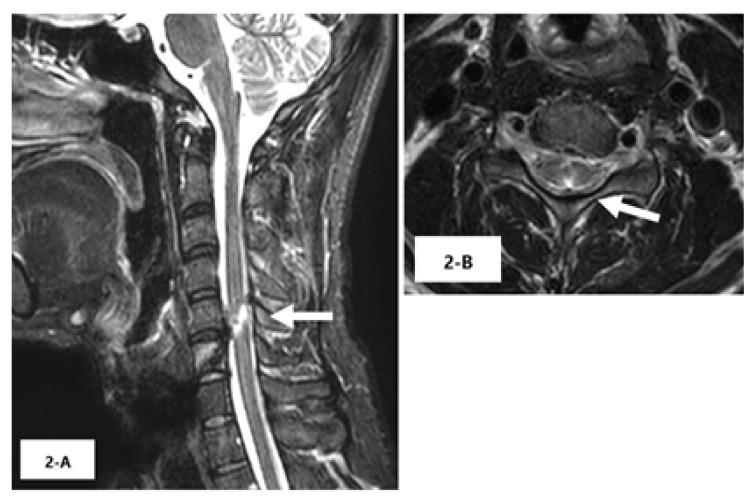

A 26-year-old man was impaled by a nail after a nail gun accident. He was fully conscious with weakness and loss of sensation in the extremities. Cervical computed tomography showed a 9-centimeter long nail penetrating the spinal cord. The nail was removed surgically six hours after the incident. Neurological deficits gradually improved, and at three-month follow-up the patient had completely recovered from muscle weakness and reported only mild sensory deficits in the bilateral sole of his foot.

This case showed a favorable neurological course, which may be attributed to the fact that the cervical spinal cord injury did not involve the corticospinal tracts and anterior horn.